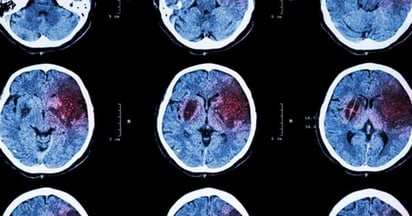

El accidente cerebrovascular es una de las principales causas de muerte y discapacidad a nivel mundial, y su pronóstico está estrechamente ligado a la rapidez con la que se actúe.

Reconocer síntomas como asimetría facial, dificultad para hablar o pérdida de estabilidad puede significar la diferencia entre una recuperación favorable y secuelas permanentes. En estos casos, cada minuto cuenta: el tiempo es cerebro.